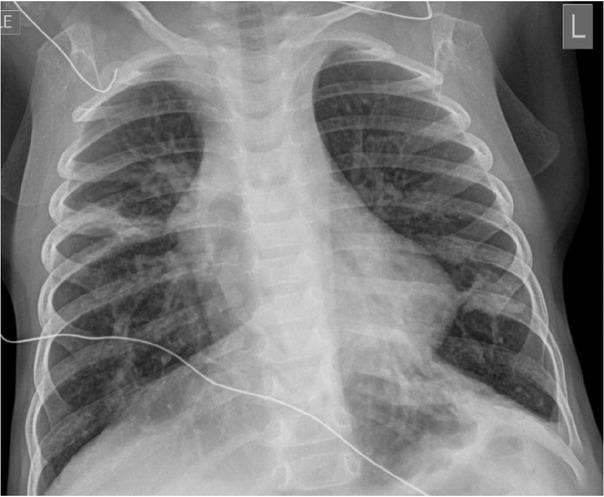

In the ED, vital signs revealed a temperature of 100.6° F (38.10C),a respiratory rate of 62 breaths per minute, heart rate 162 beats per min, blood pressure 111/60 mmHg, and 85% oxygen saturation at room air. On physical examination, he was in moderate respiratory distress with intercostal retractions, and coarse bilateral breath sounds with good perfusion. He received a fluid bolus and was placed on six litres high-flow nasal cannula which resulted in an improvement in his oxygen saturation. A chest radiograph was obtained which showed pulmonary hyper-expansion with bilateral streaky peripheral densities suggestive of viral lower airway disease (Figure 1). He was diagnosed with viral bronchiolitis and subsequently admitted for respiratory support. On day four after admission, his hypoxia worsened, raising the suspicion of a secondary pneumonia and intravenous (IV) Ampicillin (Athenex, Schaumburg, IL, USA) was started. Given his worsening respiratory status, he was made “nil per os” (NPO) and placed on IV fluids for hydration.

Fig. 1

Chest radiograph on admission. The image shows pulmonary hyperexpansion with interstitial prominence and areas of patchy density which may be due to a viral airway disease with areas of atelectasis.